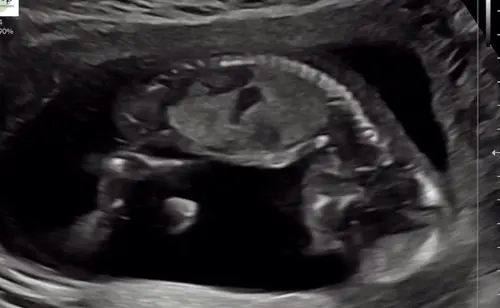

Haha onze baby lag precies zo bij de 20-weken echo! Heel gek om alles op z’n kop te zien